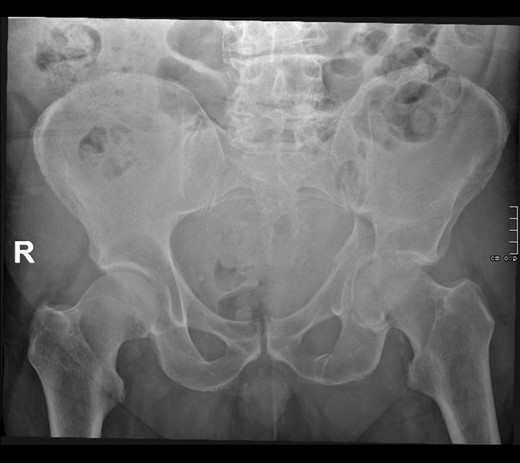

A 69-year-old man with Child–Pugh class C cirrhosis presented to the Emergency department after slipping on wet grass and falling on his left side. His glasgow coma score was 15/15 and vital signs were within normal limits: pulse rate 78/min, RR 13/min, BP 113/54 mm Hg, SpO2-100% in air. He had left hip tenderness with no ecchymosis to the abdomen, flank or thigh. A radiograph of his pelvis revealed an undisplaced fracture of his left acetabulum of both the anterior and posterior columns (Fig. 1).